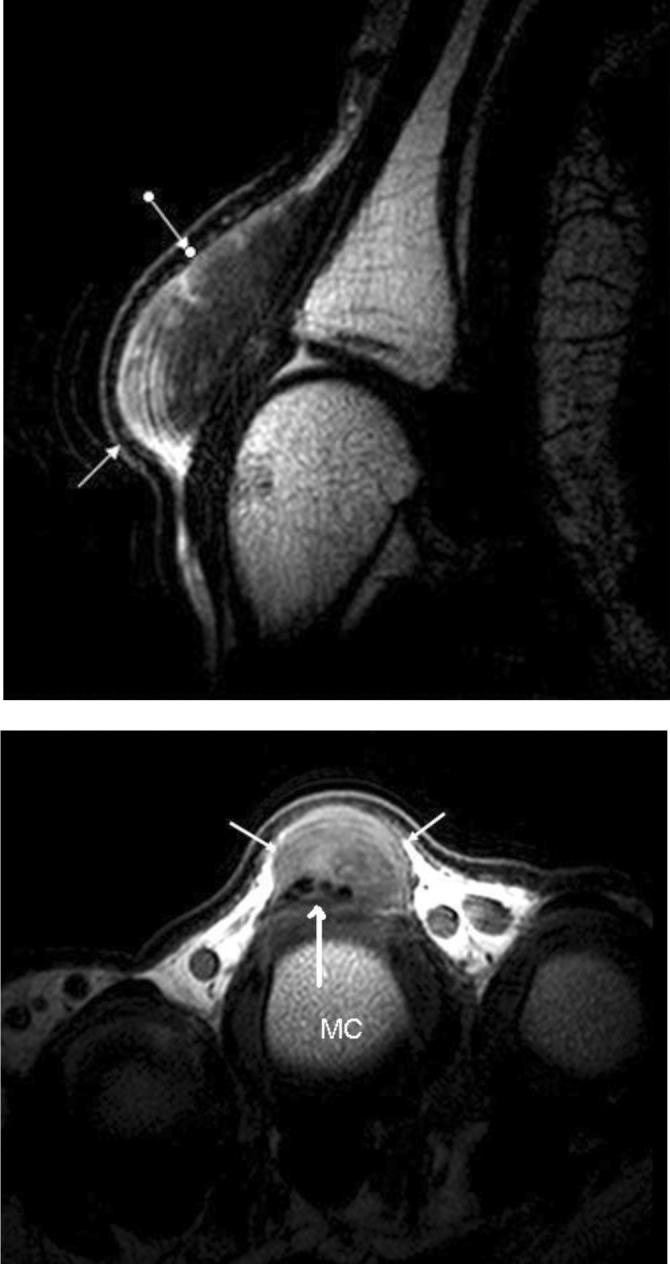

We present a rare case of multisite xanthomatosis occurring in a 38-year-old normocholesterolemic man without a familial history. More commonly, these conditions are associated with familial hypercholesterolemia and cerebrotendinous xanthomatosis. Tendon xanthomas should prompt clinicians to perform a thorough investigation of the patient's metabolic panel and family history. Rarely, these conditions occur in patients without demonstrable dysmetabolic state. The characteristic MR imaging findings are presented in conjunction with review of the literature.